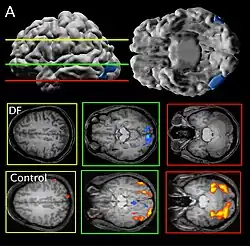

Her agnosia is thought to be caused by a bilateral lesion to her lateral occipital cortex, an area thought by dual-stream proponents to be the ventral "object recognition" stream.[1]

Patient DF's brain damage resulted from hypoxia due to accidental carbon monoxide poisoning in 1988, when she was 34 years old.[2] The lateral occipital cortex (LOC) in her brain is severely damaged and shows no activation presented with line drawings of common objects where healthy people usually do. Moreover, there is a reduction of white matter connections between LOC and other areas.[3] There is also some shrinkage in the intraparietal sulcus, often implicated in the dorsal stream for visuomotor control. The fusiform face area is intact. This would suggest the problem in DF's perception is disconnectivity between higher and lower order functioning.[4]

Recent MRIs have shown many enlarged sulci, like the intraparietal sulcus, parieto-occipital sulcus, and left calcarine sulcus, indicating atrophy.[4] Her visual field remains intact up to 30 degrees.[1]

DF does not benefit from haptic feedback—allowing her to pick up an object does not let her better estimate its width next time.[5] DF also does not use visual information about her grasp: when she can only see her grip in a distorted mirror, her performance does not change.[4] Consistent with all of this, brain imaging has shown no response to line drawings in her ventral stream. Furthermore, according to fMRI studies, the intraparietal sulcus showed preference for grasping motions over reaching motions—actually grabbing an object, in both DF and control patients, activates the intraparietal sulcus more than reaching.[4]